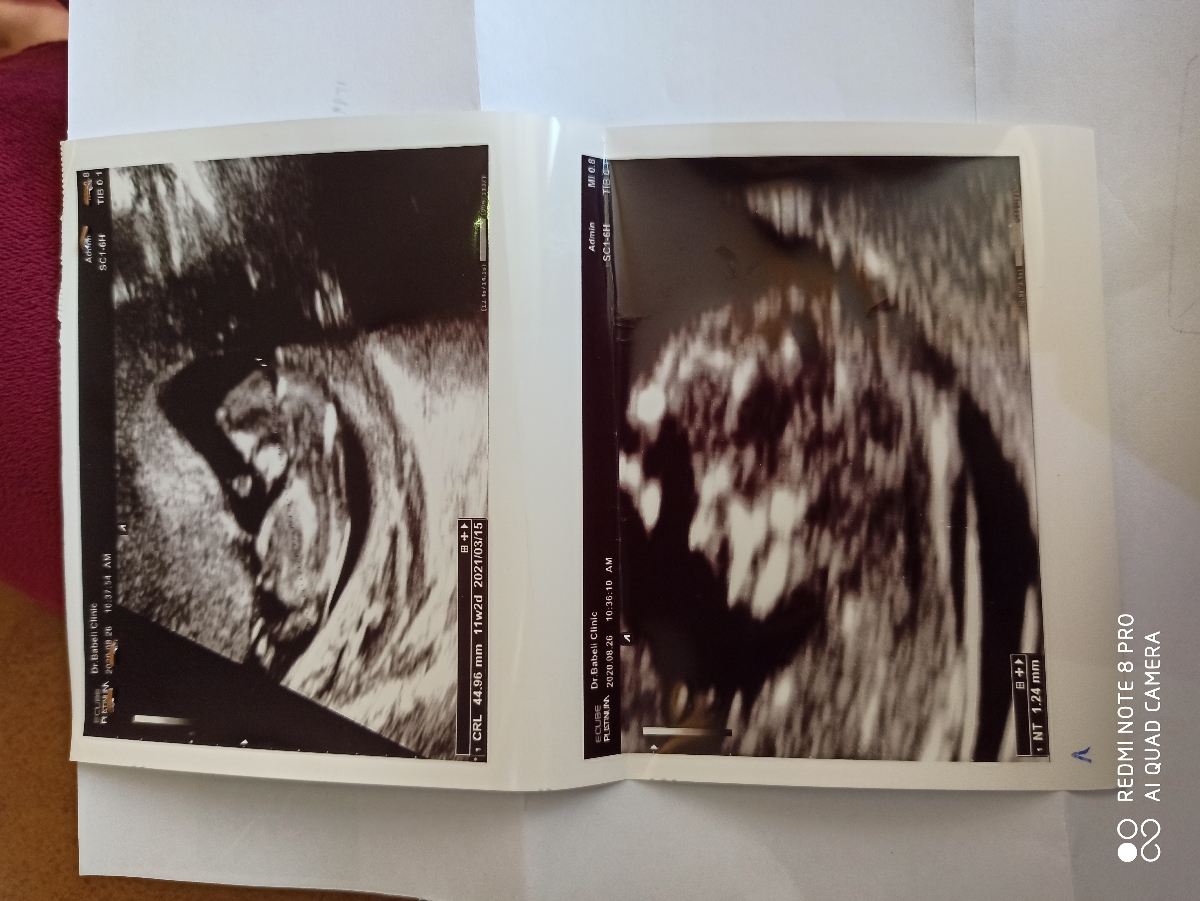

بیاین اینجا ببینین همه چی اوکیه!!؟ به نظرتون جنسیت چیه؟! جفت اوکیه؟

جواب سونو ان تی غربالگری اول

من از رو عکس. NT پسر خودم گفتم

همه چیت خوبه. جفت منم قدامیه

دکترم گفت حدسم پسره به خاطر ضربان

ضربان قلبش چندبود

۱۵۲

سلام همه موارد نرمال است